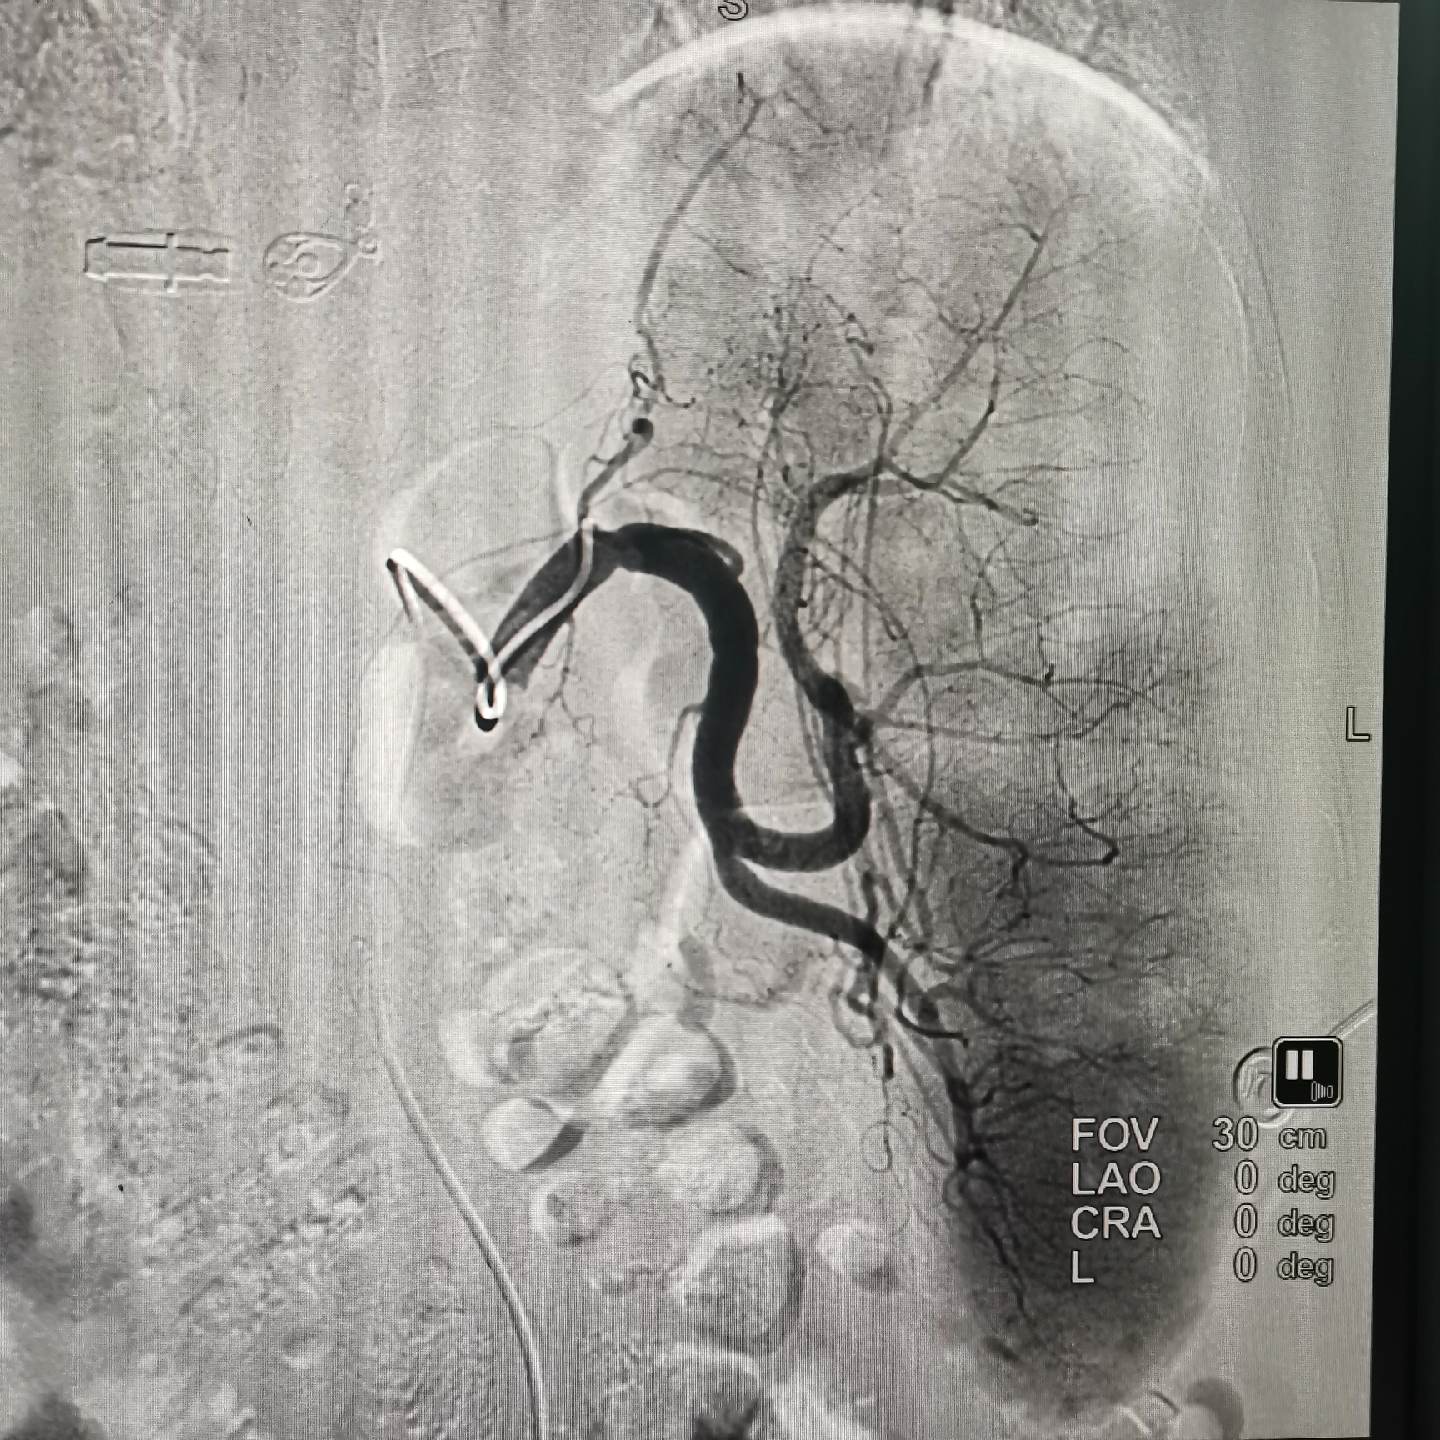

一例贲门癌患者经三年化疗及靶向治疗病情进展!贲门及胃底管壁增厚血供丰富,贲门管腔完全被肿瘤占据合并旰胃间隙淋巴结转移融合!今日行贲门区及转移淋巴结载药微球栓塞及鼻十二指肠管置入!